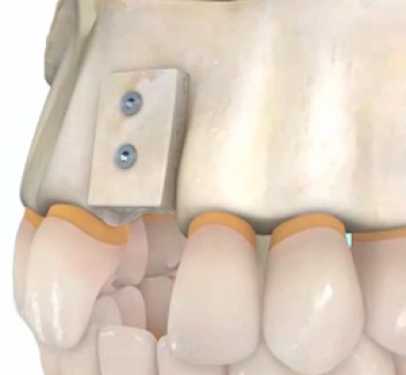

CIRURGIA GUIADA POR COMPUTADOR

Nesse tipo de cirurgia os implantes são instalados sem cortes ou incisões de bisturi na gengiva. Não há necessidade de pontos e sutura. O tempo do procedimento é bastante reduzido, com menos dor e praticamente nenhum sangramento.

Todo procedimento é planejado no computador em um modelo virtual 3D obtido por meio de uma tomografia da arcada dentária.

Os implantes são inseridos através de um guia tridimensional com máxima precisão, sem necessidade de cortes de bisturi.

O Dr. Frederico Lessa é implantodontista credenciado no sistema Neoguide e Neodent Digital.